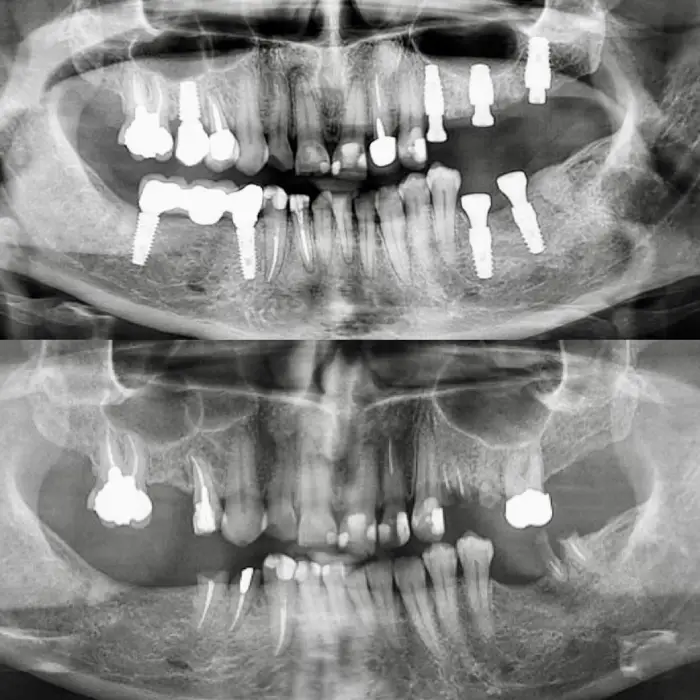

باز سازی کامل فک با ۱۲ واحد ایمپلنت naxis